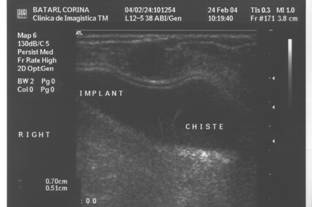

Ecografia este usor de realizat. Ecografic se pot decela:

- ruptura implantului; formatiuni nodulare anecogene in tesutul mamar periprotetic nedepresibile de presiune ( spre deosebire de colectiile lichidiene periprotetice );

- ecografia identifica doar colectiile de dimensiuni mari. Ea pune diagnosticul in epansamentele precoce, hematom, limfocel sau serozitate inflamatorie ( colectie transsonica periprotetica deformabila );

- ecografia este, in fine, utila in diagnosticul mastopatiilor benigne sau maligne. Ea va putea, eventual, preciza natura unei opacitati de pe mamografie;

- ecografia nu va evidentia microcalcificarile.